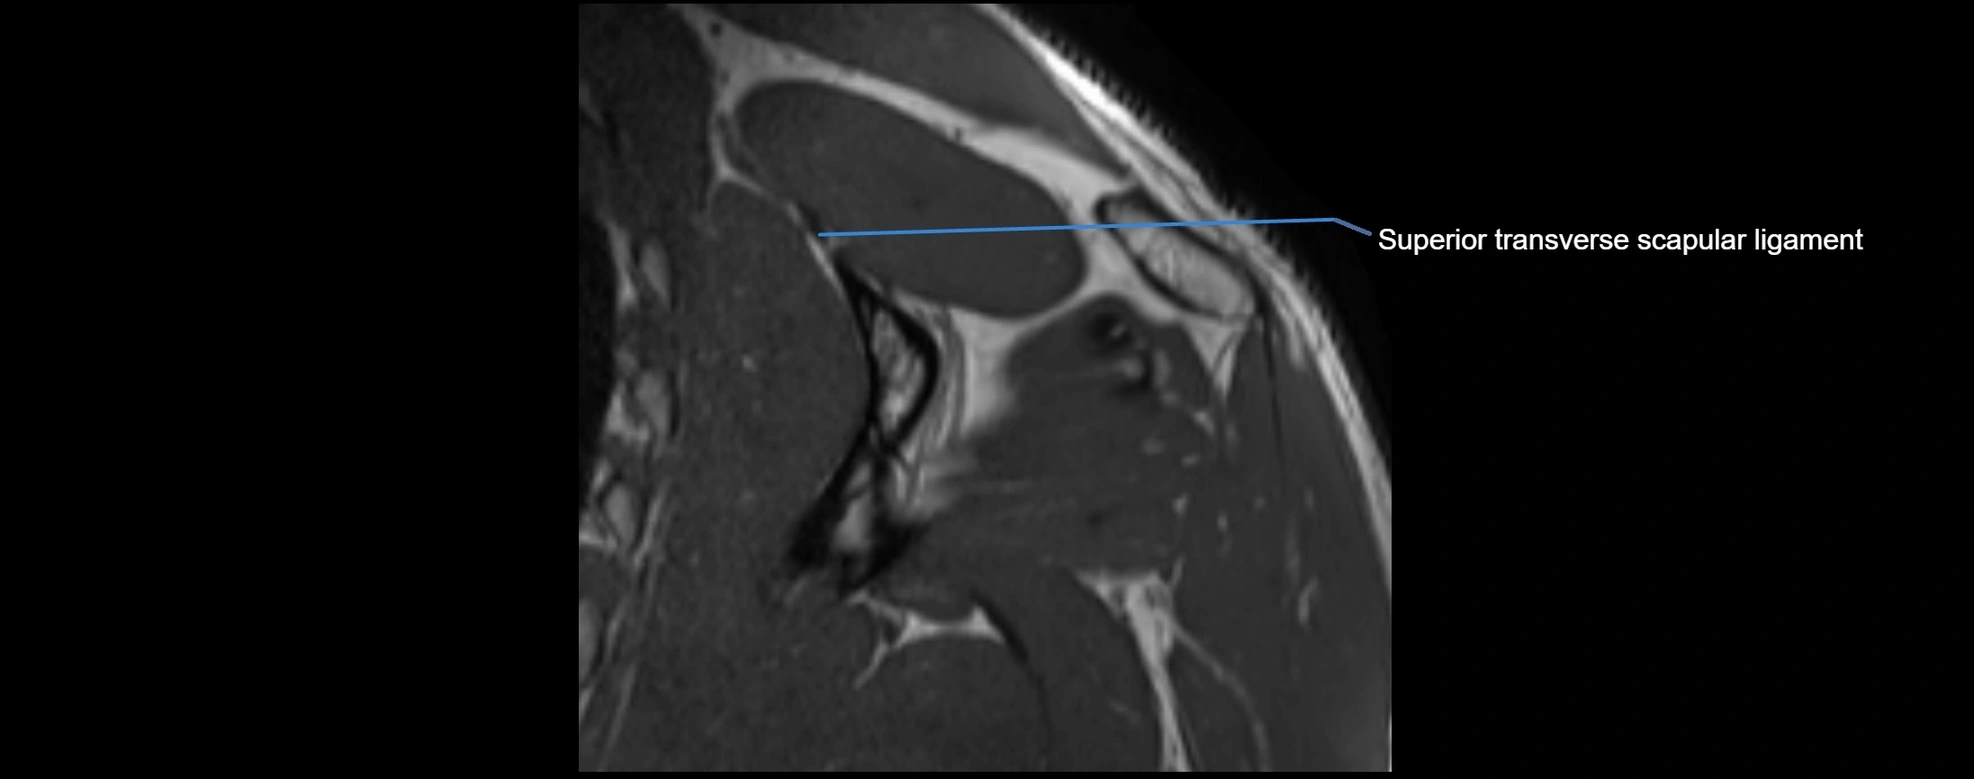

CT image

image